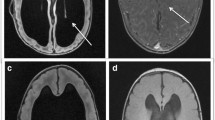

Quantitative assessment of intracranial volume (ICV), lateral ventricles volume (LVV), choroid plexus volume (CPV), and posterior cranial fossa volume (PCFV) in MMC patients used MATLAB R2023a (MathWorks, Natick, MA, USA) with digital imaging and communication in medicine (DICOM) CT data obtained immediately after birth. The target areas were manually segmented using the image segmenter app in MATLAB (https://www.mathworks.com/help/images/ref/imagesegmenter-app.html). Representative segmentation of ICV, LVV, CPV, and PCFV are shown in Fig. 1. Volume calculations (in milliliter, mL) were performed, and this method aligns with our previous studies [12,13,14,15]. LVV represented the volume of bilateral ventricles, and choroid plexus at the lateral ventricles and the foramen of Monro were assessed.

Representative segmentations. Segmentations for intracranial volume (ICV), lateral ventricles volume (LVV), choroid plexus volume (CPV), and posterior cranial fossa volume (PCFV) are colored as green, purple, yellow, and pink, respectively. Representative segmentations are presented from cases of no hydrocephalus (a), progressive hydrocephalus (b), and hydrocephalus at birth (c)